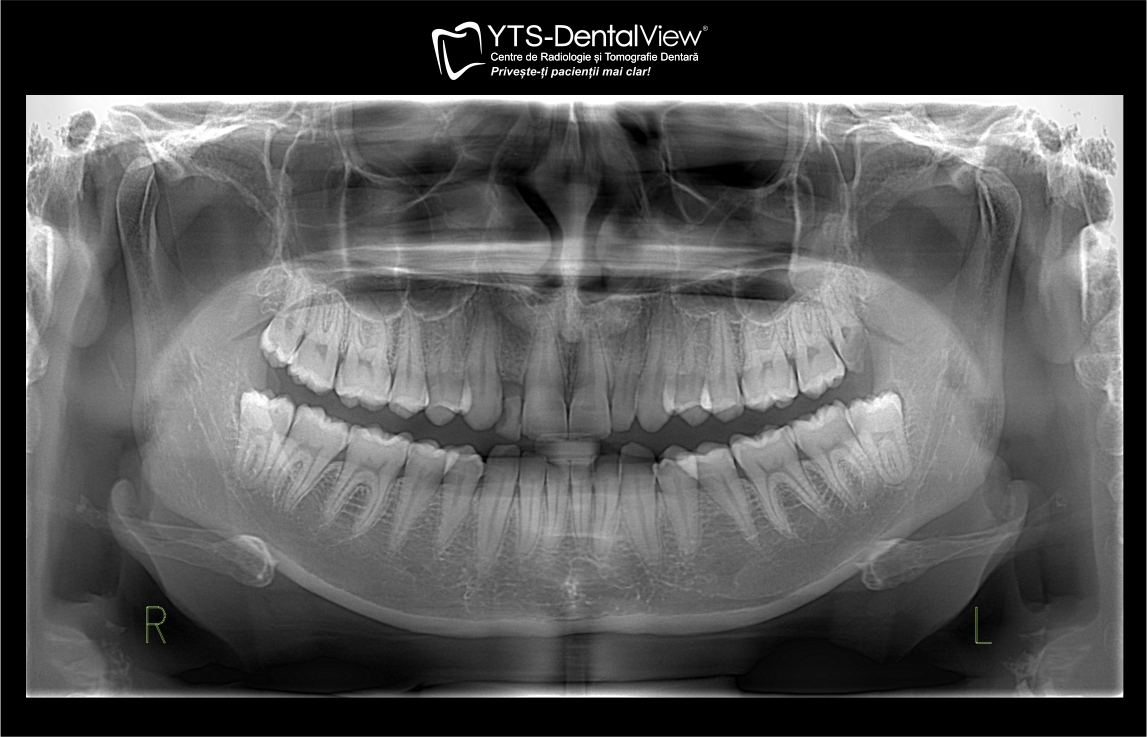

Radiografia panoramica ofera o imagine clară și detaliată despre rădăcinile dinților, structura osoasă a maxilarului, sinusuri și nervi, facilitând un diagnostic precis și tratamente eficiente.

O radiografie panoramica digitala efectuata la YTS Dental View dureaza doar cateva minute si ofera o imagine clara si detaliata asupra intregii cavitati orale. Aceasta radiografie dentara rapida permite medicului stomatolog sa observe structuri care nu pot fi vazute la un control obisnuit, cum ar fi radacinile dintilor, sinusurile, nervii si maxilarul.